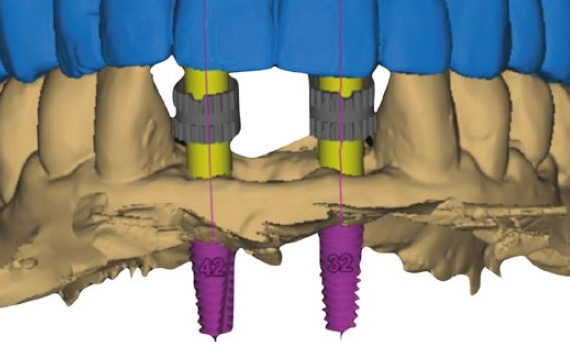

Von der analogen zur digitalen Implantatprothetik: Was ist sinnvoll und was ist Hype?

Dr. Peter Gehrke und ZT Carsten Fischer

Dr. Peter Gehrke und Zahntechniker Carsten Fischer erörterten im Teamwork die verschiedenen Indikationen und diskutierten die Frage, was digitaler Workflow eigentlich ist. Für viele sei das gleichbedeutend mit navigierter Planung, um darüber die Voraussetzung für eine fachgerechte prothetische Versorgung zu schaffen. Doch das sei nur ein Teil des digitalen Workflows. Zwar ist der Einsatz computergestützter Scan- und Fertigungstechnologien zur Herstellung von implantatgetragenem Zahnersatz oder Teilen für viele Anwender in Labor und Praxis bereits Realität. Doch allein schon die Modellkontrolle ist wieder analog ebenso wie es bei herausnehmbaren Arbeiten analoger Schritte bedarf. Auch wenn Intraoralscans für bestimmte Arbeiten analoge Abformungen überflüssig machen, stößt die digitale Abformung an ihre Grenzen, wo starke Angulationen prothetisch ausgeglichen werden müssen. Das gilt gleichlautend für suboptimal positionierte Implantate, die sich auf Basis von Intraoralscans nicht prothetisch exakt versorgen lassen. Ein digitaler Workflow funktioniere nur im Team, so Dr. Gehrke.

Intraorales Scanning ist weit mehr als nur Abformung, es ist Dokumentation und Qualitätskontrolle. Werden direkt nach Insertion die Implantatpositionen ins Labor übertragen, erhält der Zahnarzt ein unmittelbares Feedback als entscheidendes Kriterium vor der Anfertigung individueller CAD/CAM-Aufbauten in den Fällen, wo standardisierte Komponenten nicht mehr ausreichen. Mit individuellen Healing-Abutments lässt sich das gewünschte Emergenzprofil ausformen und die Daten können für die finale Versorgung übernommen werden. Das Risiko, die Mukosa durch die Krone zu stark zu verdrängen, ist damit ausgeschlossen: ein digitaler Workflow mit klinischem Nutzen.

Für provisorische Versorgungen, insbesondere im ästhetisch sichtbaren Bereich, wird unmittelbar nach Insertion ein Scan an das Labor gesendet, wo aus einem entsprechenden Kunststoffblock die provisorische Versorgung samt zugehöriger Anschlussgeometrie herausgefräst und bei Bedarf jederzeit reproduziert werden kann. Zudem lassen sich alle weiteren Schritte auf diesem Datensatz aufbauen. Ein weiterer „digitaler“ Vorteil liegt in der verlustfreien Verknüpfung verschiedener Komponenten in der Konstruktionssoftware.

Individuelle Komponenten wie Abutments lassen sich CAD/CAM-geführt in dem gewünschten Design und den bevorzugten, auch neuen Materialien herstellen. So weisen einteilige und mit Nitrit-beschichtete Titanabutments eine hohe Biokompatibilität bei nur noch geringem Farbshift auf und bieten eine hohe Biege-Bruch-Festigkeit. Bei Volumendefiziten wiederum können die gewünschte Mukosastruktur und die ideale Menge des gewünschten Weichgewebes mit virtueller Planung noch vor dem chirurgischen Eingriff festgelegt werden.

Grenzen findet der digitale Workflow bei multiplen Implantaten und der frästechnischen Herstellung einer passiv sitzenden NEM-Brücke. Position und Ausrichtung der Implantate exakt abzuformen, gelingt nur analog, eine entsprechende intraorale Erfassung scheitert (noch) am inhärenten Mismatch der Scanbodies.

Bei implantatgetragenen, CAD/CAM-gefrästen Stegen ist die Topografie der transmukosalen Oberfläche für die Integration der Weichgewebe und der Reduzierung von Plaque- und Bakterienretentionen ausschlaggebend. Hier zeigen profilometrische Analysen Qualitätsunterschiede in der externen Herstellung, die eine manuelle Nachbearbeitung im Labor notwendig machen.

Ebenfalls nicht im rein digitalen Workflow, sondern nur mit analogen Zwischenschritten realisierbar ist die prothetische Versorgung schmaler Implantate in engen Lücken mit individualisierten Standardaufbauten, wie sie nach kieferorthopädischer Behandlung von Nichtanlagen auftreten können.